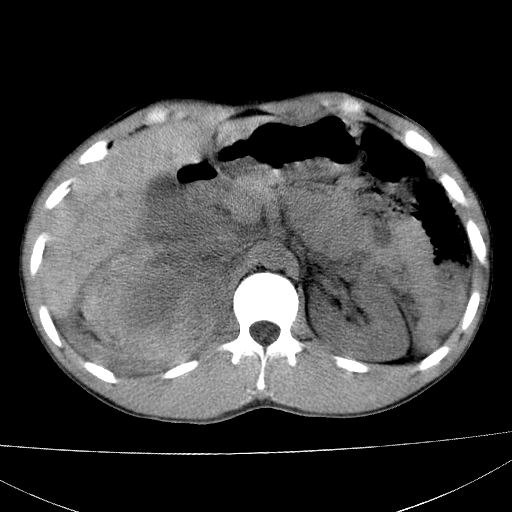

标题: CT15860:男,21岁,腹部外伤2小时伴胸疼。 [打印本页]

标题: CT15860:男,21岁,腹部外伤2小时伴胸疼。

肝脏及肾脏明显有损伤性改变并激发腹腔内积液(血),以肝脏撕裂及肾周积血显著。

1)肝破裂伴腹腔积液(血)。2)右肾破裂伴右肾包膜下及肾周血肿。3)腹部空腔脏器穿孔可能。4)右侧少量胸腔积液(血)。

肝肾挫裂伤,右肾周及包膜下血肿,腹腔积液,不排除空腔脏器穿孔,建议行增强检查

肝肾挫裂伤,右肾周及包膜下血肿,腹腔积液

肝右肾挫裂伤,右肾包膜下及肾周血肿.胸腹腔少量积液.脾脏下部密度稍不均,必要时,增强.

肝肾挫裂伤,右肾周及包膜下血肿,腹腔积液(血)。